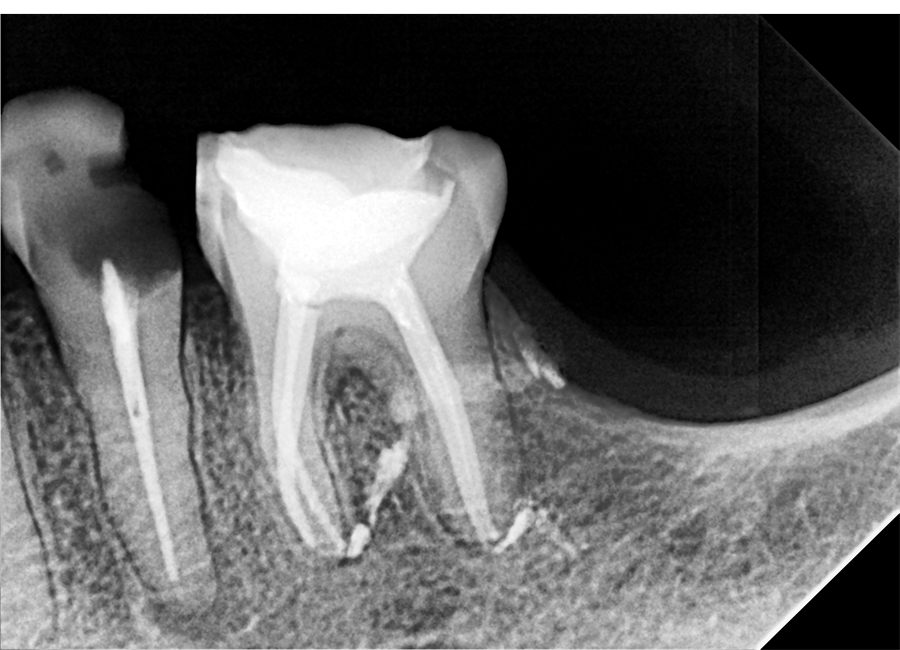

Figure 2. Immediate post-operative radiograph of tooth #36 following retreatment.

Figure 2